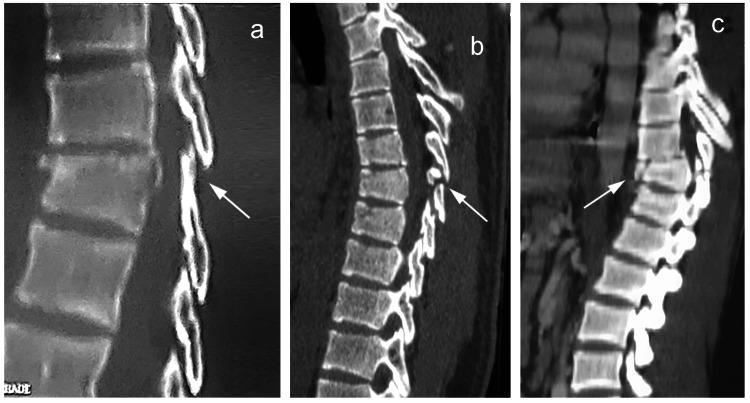

The soft tissues surrounding the spine play a primordial role in its stability, the most important of which are located posteriorly and are deemed the posterior ligamentous complex (PLC). Injuries to the PLC in the setting of thoracolumbar trauma are often dreaded and little attention has been given to them in the management protocols of thoracolumbar trauma. This review aims to summarize and contextualize current concepts in PLC injuries of the thoracolumbar spine with the aim to provide a clear guide for clinical management. Injuries to the PLC may be suspected on the clinical exam but are often missed, leading to serious complications, including instability and neurological compromise. The diagnosis is often made indirectly by spinal radiographs and CT-scanning or by direct visualization of soft tissues via magnetic resonance imaging. The latter remains the standard imaging modality and is mandatory for patients with a high suspicion of PLC injury. PLC injuries are associated with vertebral fractures and follow a progressive pattern of severity, depending on the mechanism of injury and extent of trauma. Surgical management is warranted, as PLC damage renders the spine unstable. Although fusion was once the standard of care and remains applicable for certain patients, recent endeavors of temporary spinal fixation without fusion are increasingly gaining traction in patients with PLC injuries. In conclusion, PLC injuries are challenging as they are often missed, poorly understood, and are not easily managed. Proper diagnosis and management are crucial to avoid long-standing complications such as spinal instability. Considering the paucity of available data on such an important topic in thoracolumbar trauma, this review article aims to contextualize current concepts in PLC injuries in order to demystify this sparsely covered subject.

脊柱周围的软组织对其稳定性起着至关重要的作用,其中最重要的位于脊柱后方,被称为后韧带复合体(PLC)。在胸腰椎创伤情况下,PLC损伤往往令人担忧,而在胸腰椎创伤的管理方案中,对其关注较少。本综述旨在总结和梳理胸腰椎PLC损伤的当前概念,以便为临床管理提供清晰的指导。PLC损伤在临床检查中可能被怀疑,但常常被漏诊,从而导致严重并发症,包括脊柱不稳定和神经功能损害。诊断通常通过脊柱X线片和CT扫描间接做出,或通过磁共振成像直接观察软组织。后者仍然是标准的成像方式,对于高度怀疑PLC损伤的患者是必需的。PLC损伤与椎体骨折相关,并根据损伤机制和创伤程度呈现出逐渐加重的严重程度模式。由于PLC损伤会使脊柱不稳定,因此需要进行手术治疗。虽然融合术曾经是标准的治疗方法,并且仍然适用于某些患者,但最近在PLC损伤患者中,不进行融合的临时脊柱固定方法越来越受到关注。总之,PLC损伤具有挑战性,因为它们常常被漏诊、理解不足且不易处理。正确的诊断和管理对于避免诸如脊柱不稳定等长期并发症至关重要。鉴于在胸腰椎创伤这一重要主题上可用数据匮乏,本文旨在梳理PLC损伤的当前概念,以揭开这个研究较少的主题的神秘面纱。